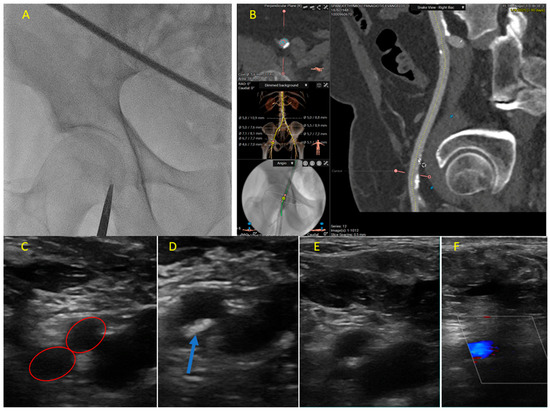

- Xenogiannis, I.; Varlamos, C.; Keeble, T.R.; Kalogeropoulos, A.S.; Karamasis, G.V. Ultrasound-Guided Femoral Vascular Access for Percutaneous Coronary and Structural Interventions. Diagnostics 2023, 13, 2028. [Google Scholar] [CrossRef] [PubMed]